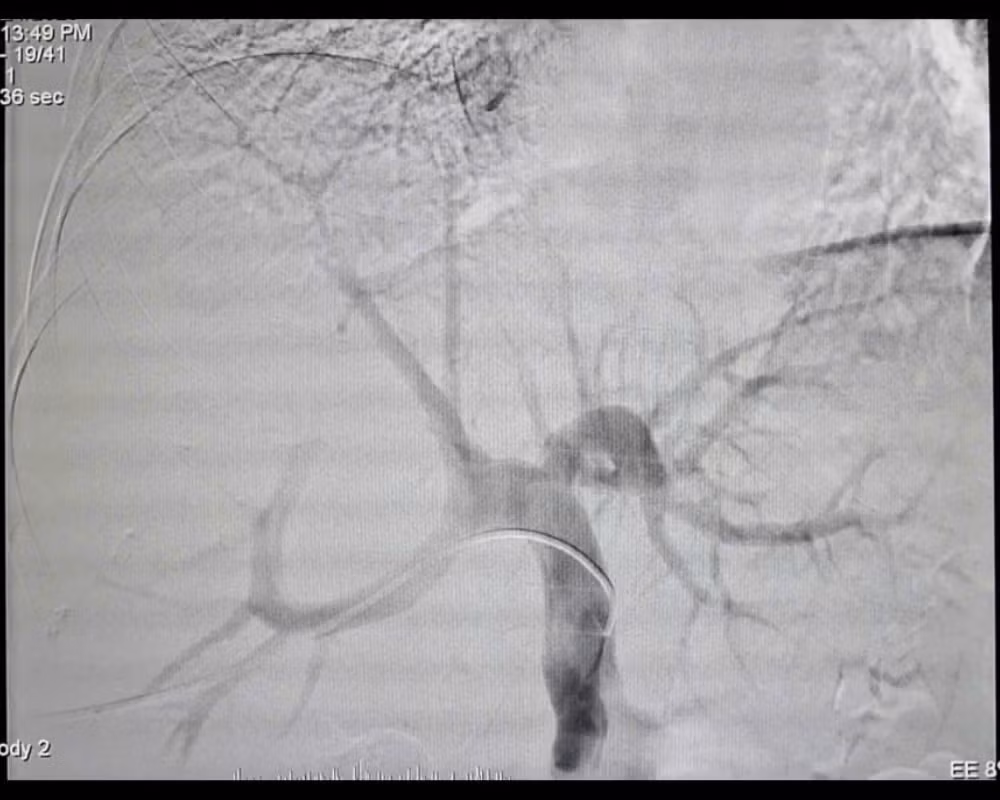

Quá trình can thiệp gây tắc tĩnh mạch cửa bên phải (PVE) - Ảnh BVCC

Trước tình huống này, các ê kíp chuyên môn đã hội chẩn liên khoa và quyết định thực hiện kỹ thuật can thiệp nút mạch gây tắc tĩnh mạch cửa bên phải (PVE). Thủ thuật này giúp chặn dòng máu nuôi phần gan phải có khối u và đồng thời thúc đẩy phần gan lành bên trái phát triển về thể tích. Chỉ sau 4 tuần, thể tích gan trái tăng lên 36,8% tổng thể tích gan, đủ điều kiện tiến hành phẫu thuật.